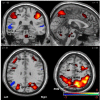

The adaptive trade-off between exploration and exploitation is a key component in models of reinforcement learning. Over the past decade, these models have been applied to the study of reward-seeking behavior. Drugs of addiction induce reward-seeking behavior and modify its underlying neurophysiological processes. These neurophysiological changes may underlie a behavioral shift from a flexible, exploratory mode to a focused, exploitative mode, which precedes the development of inflexible, habitual drug use. The goal of this study was to investigate the relationship between explore/exploit behavior and drug addiction by examining the neural correlates of this behavior in cigarette smokers. Participants (n=22) with a range of smoking behaviors completed a smoking dependence motives questionnaire and played a 6-armed bandit task while undergoing functional magnetic resonance imaging (fMRI). Exploratory behavior produced greater activation in the bilateral superior parietal and bilateral frontal cortices than exploitative behavior. Exploitative behavior produced greater activation in the bilateral superior and middle temporal gyri than exploratory behavior. fMRI data and orthogonalized smoking dependence motive scores were entered into multiple linear regression analyses. After controlling for nicotine tolerance, smoking automaticity positively correlated with activation in the same bilateral parietal regions preferentially activated by exploratory choices. These preliminary results link smoking dependence motives to variation in the neural processes that mediate exploratory decision making.